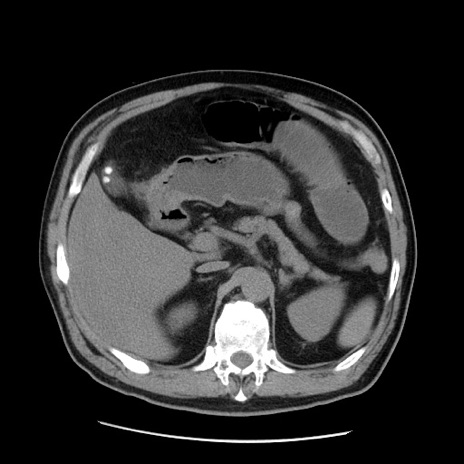

症例20(横断像)

【症例】 60歳代男性

【主訴】 腹部膨満、嘔吐

【現病歴】5日前頃より倦怠感を認め食事量減少し4日前の朝嘔吐、食事摂取困難となった。 3日前近医受診し点滴施行され整腸剤などを処方された。 当日他院を受診し、腹部膨満著明、炎症反応の上昇(CRP10.8、WBC11200)あり、紹介受診となる。

【身体所見】 意識JCS1 受け答えがはっきりしないBP 111/57mHg、 P 67bpm、、BT35.2°C、SpO2 97%(RA)、 腹部:膨隆、打診で鼓音あり、全体的に圧痛有り、腸蠕動音(-)、反跳痛ははっきりせず。

【データ】WBC 11400、CRP 14.20